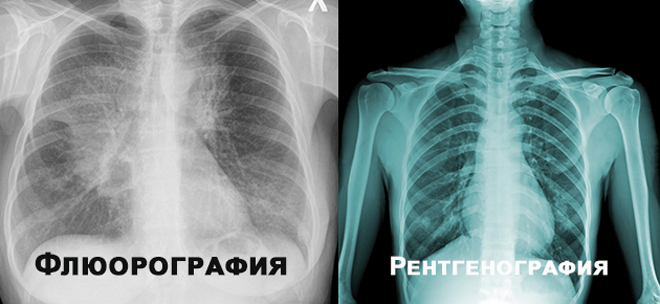

Чим відрізняється флюорографія від рентгену? Флюорографія та рентген — здавалося б, два схожі терміни. Але важливо розуміти, що ж насправді відрізняє ці